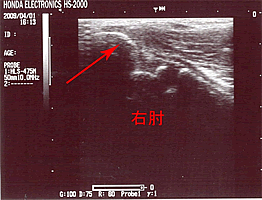

4月1日、癒合(治癒)後の画像(↓)です。

右肘のみの画像ですが、矢印先の「すきま」が十分に狭くなり、内側側副靭帯MCL(尺側側副靭帯UCL)の描出も改善されています。以降は投球も解禁。